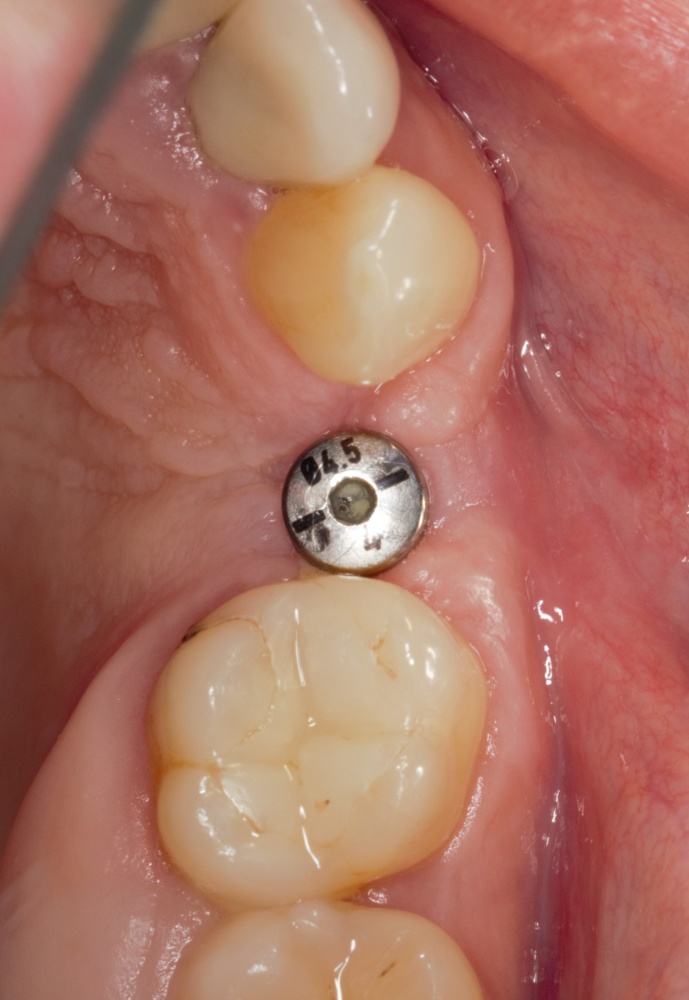

Простой. Надежный. Дешевый. Способ остеопластики.